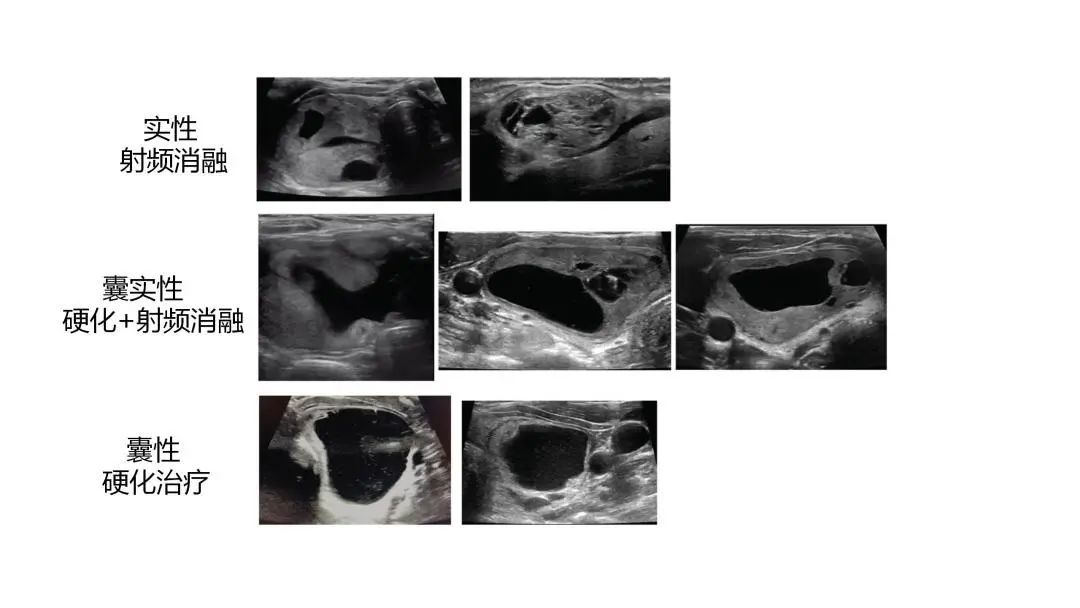

根据文献,在世界碘充足地区,可触及甲状腺结节的患病率在女性中约为5%,在男性中约为1%。高分辨率超声检查获得的甲状腺结节的患病率为20% ~ 76%,甲状腺囊肿或囊实性肿块占15%~22%,并且以良性结节多见。 目前针对甲状腺结节微创治疗的方式主要有肿瘤的局部消融,包括射频、微波、激光以及硬化治疗,可以分别针对不同类型的结节进行治疗。 实性结节,即结节成分为“肉”组成的,微创治疗方式主要为肿瘤的消融治疗,通过局部产生热量来“杀灭”肿瘤细胞。 内部以囊性为主或基本上呈囊性的结节,通俗讲结节内部成分主要为“水”,这种结节建议首选超声引导下囊肿硬化治疗,通过超声引导把“水”抽出来,冲洗干净后,再局部注入硬化药物。硬化治疗的目的是把结节囊壁细胞脱水、坏死,产生无菌性炎症,使囊壁细胞不能再分泌液体,从而使囊肿逐渐吸收,消除囊肿局部压迫产生的症状。优点是经济,花费只有消融治疗费用的十分之一,但疗效肯定。不足就是只能缩小结节,最终局部囊肿缩小后会存在缩小后的“小结节”,为囊壁的“皮”皱缩形成的。 对于囊实性各占一半的结节,即一半是“水”,一半是“肉”组成的结节,如果治疗的需求仅仅是缩小结节,可以选择超声引导下硬化治疗,把囊性成分处理掉,能够减轻症状和改善颈部外观,不再鼓着“大包”;如果治疗的需求比较高,建议选择先硬化治疗囊性成分,6个月后选择消融治疗。好处是治疗得比较彻底,但治疗周期比较长,费用相对高。